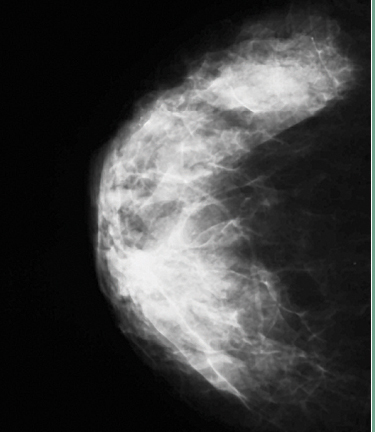

While mammography is considered the best single modality for population-based screening, its sensitivity is diminished by up to 20 percent in patients with dense breasts (breasts with a higher ratio of fibroglandular tissue to fat). This reduction in sensitivity is due for the most part to masking, a phenomenon in which surrounding dense breast tissue obscures a cancer on mammography.

In response, several states have adopted laws requiring patient and referring physician notification when the interpreting radiologist determines that the pattern of fibroglandular tissue on a patient’s mammogram is considered dense.

The broad classification of breast density under California law does not take into account the varying risk levels among patients with different breast densities. When risk is expressed relative to average breast density, the risk for the 40 percent of women with heterogeneously dense breasts is about 1.2 times greater than average and the risk for the 10 percent of women with extremely dense breasts is about 2.1times greater than average. Therefore, breast density is a risk factor, but not a strong one.